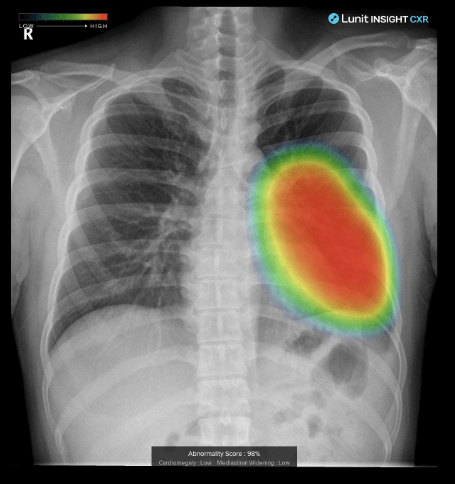

주요 사업은 루닛 인사이트와 루닛 스코프라는 솔루션이 있습니다. 루닛 인사이트는 암진단 솔루션이며, 루닛 스코프는 항암제 치료 효과 예측 솔루션입니다.